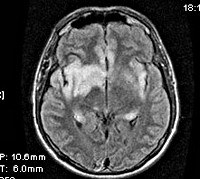

Информация о диссеминированном рассеянном энцефаломиелите